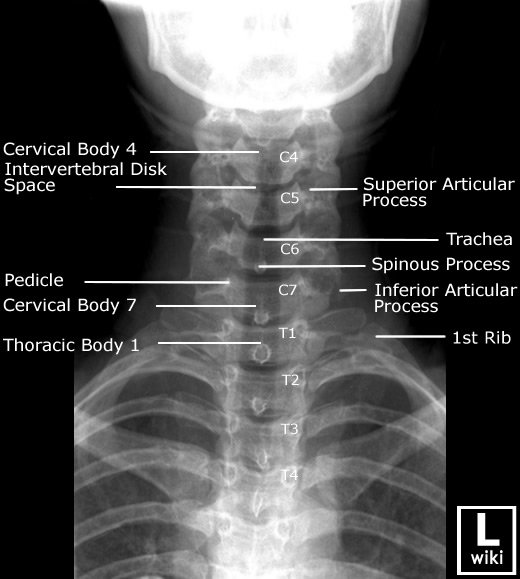

Spine Radiographic Anatomy

| AP view (Cervical) | AP view (Thoracic) |